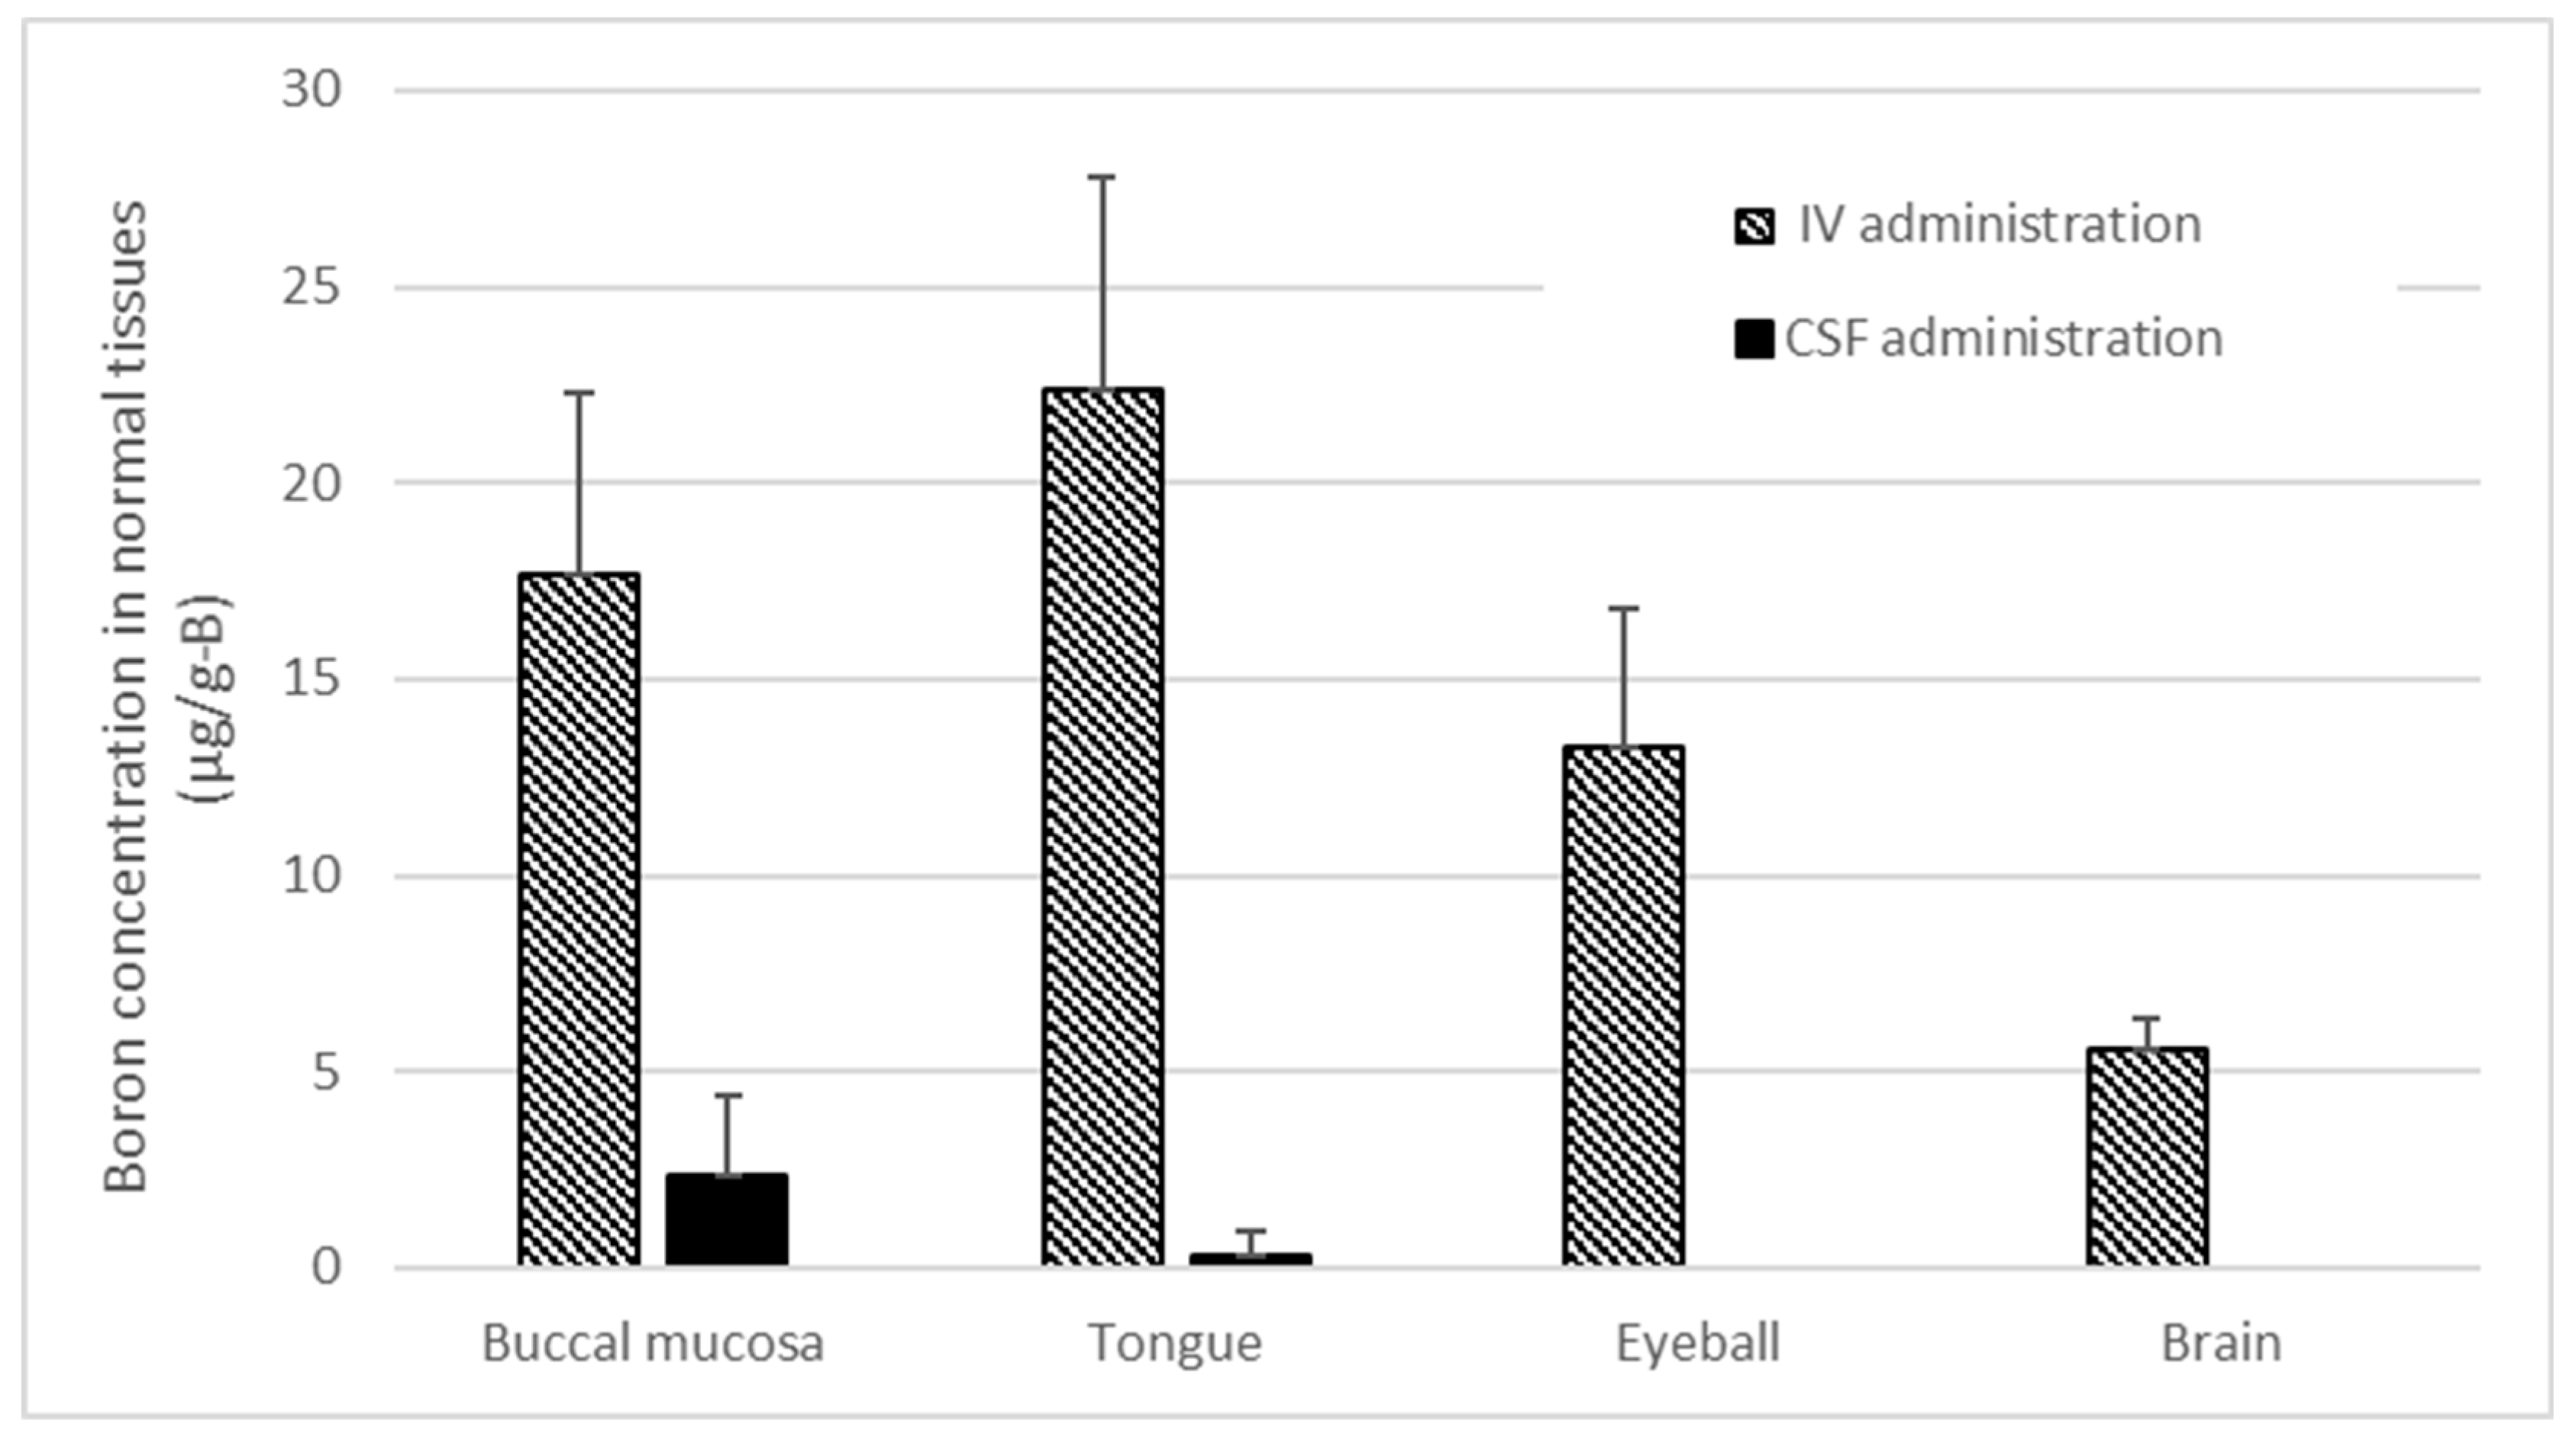

2.5. Boron Concentrations in Various Normal Tissues of Rat Heads Administered BPA via Both the CSF and IV Methods

4.2. Boron Concentration in Normal Tissues and the T/N Ratio in BNCT

3. Results